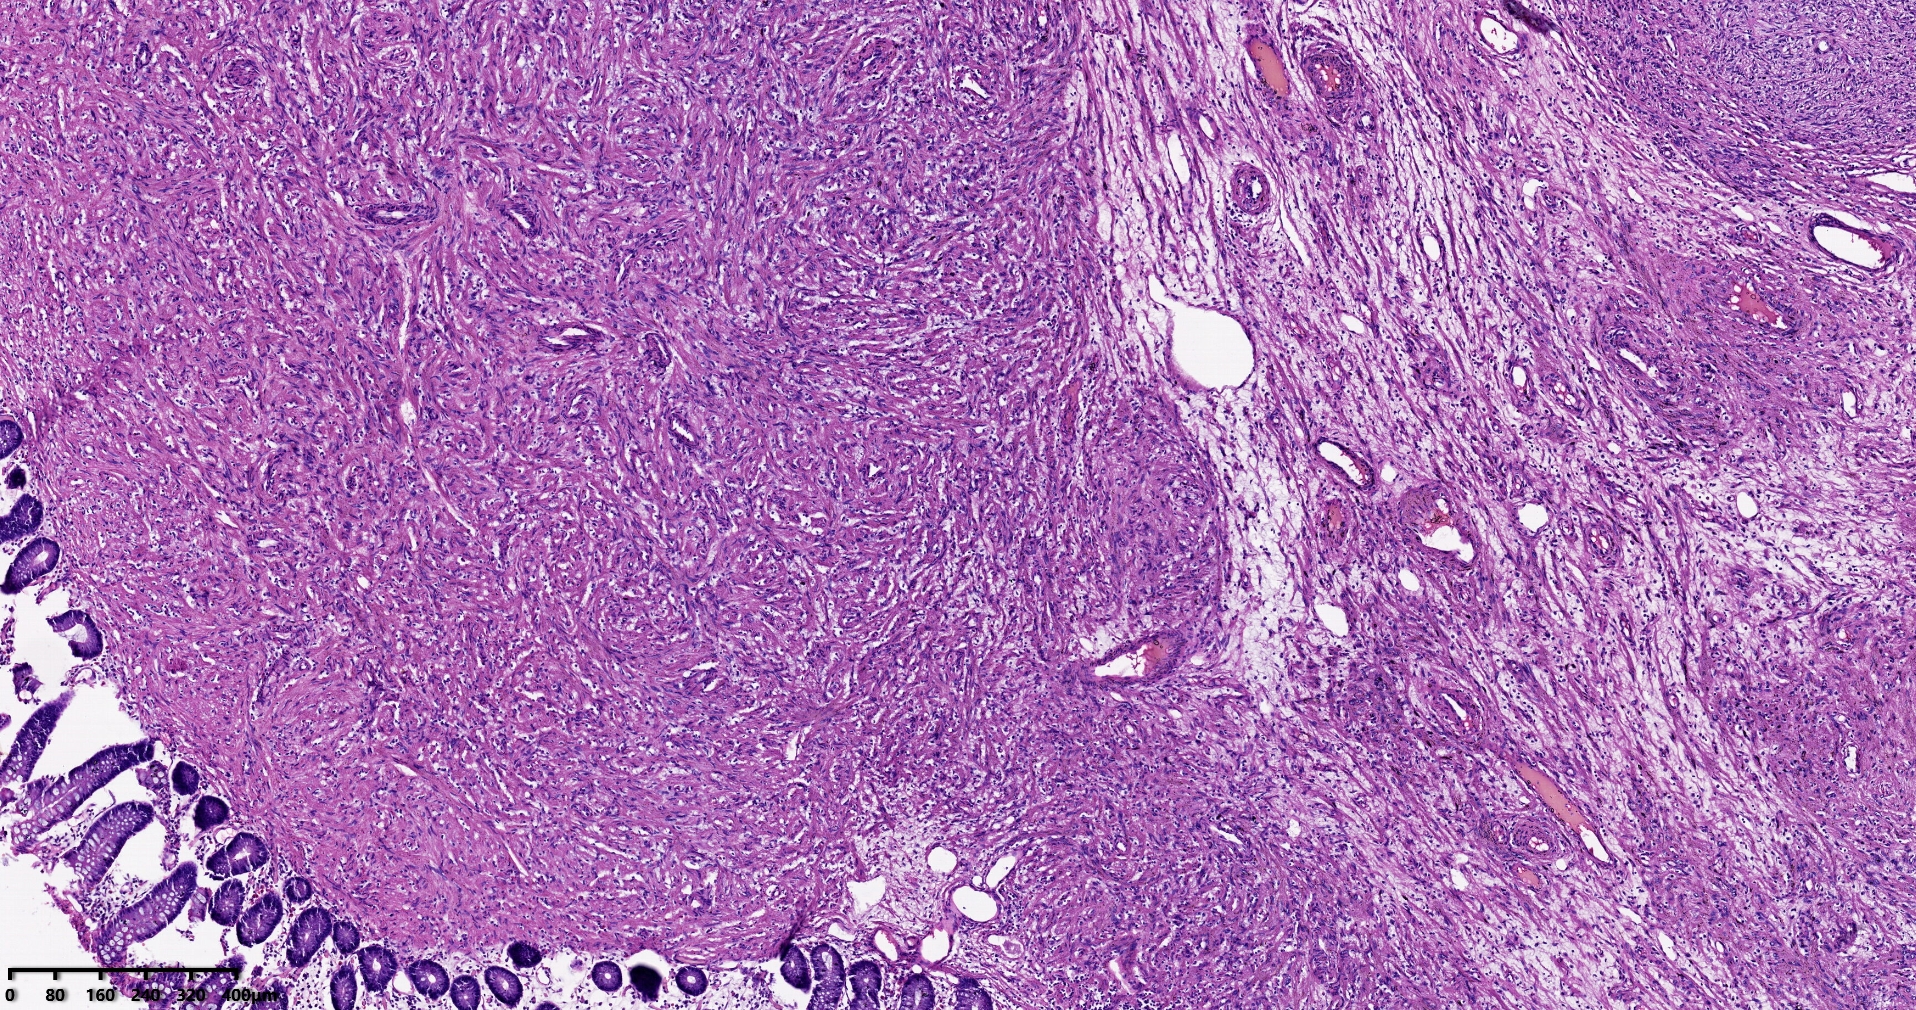

结肠肝曲息肉状肿物,平滑肌瘤?胃肠道间质瘤?炎性纤维性息肉?

性别

男

年龄

56岁

临床诊断

结肠肝曲息肉

一般病史

不详

标本名称

大体所见

灰红色椭圆形息肉一个,直径2.5cm,蒂长0.5cm,切面灰白灰红色,质中。

请路过的老师指教。

图1

考虑间质瘤?

就HE形态而言,间质瘤的可能性要大一些,建议做免疫组化协助鉴别。